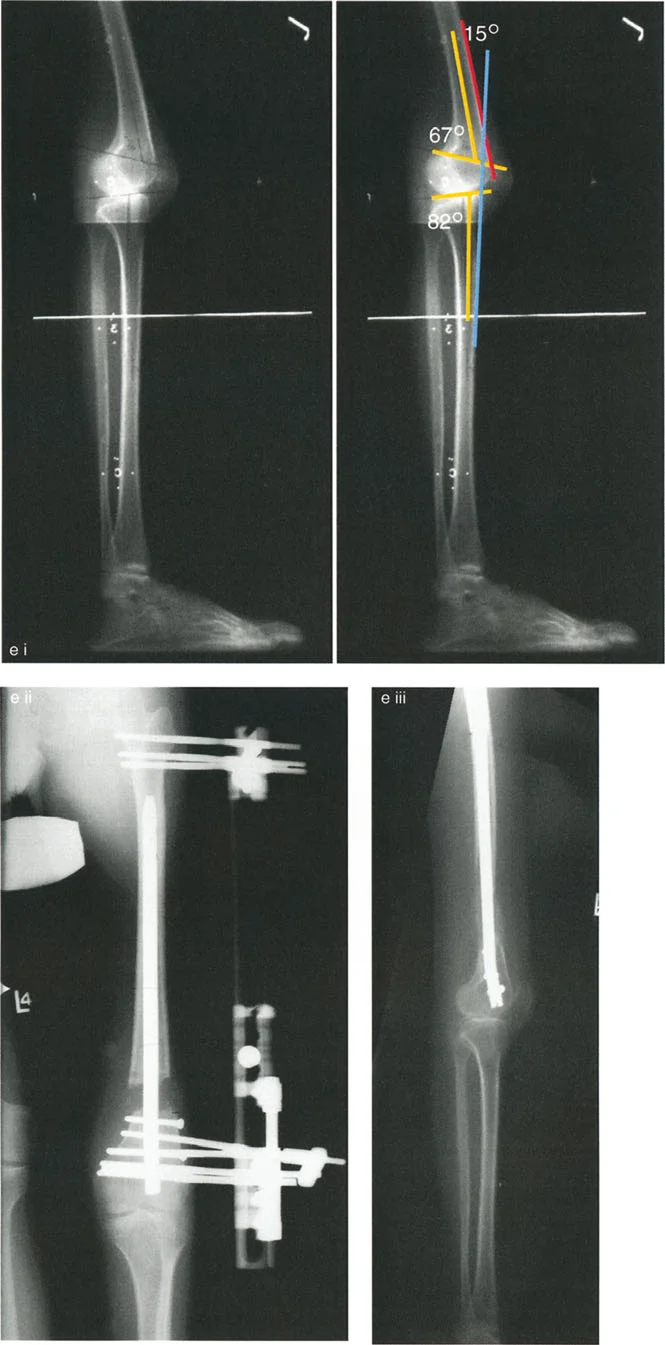

- الأشعة السينية الطويلة للطرف السفلي بالكامل أثناء الوقوف (Standing Long-Leg AP View): تُعد هذه الأشعة حاسمة لتقييم المحاذاة الميكانيكية للطرف السفلي بأكمله. تُظهر بدقة درجة الانحراف الأفحج (Varus) أو الأروح (Valgus) وتساعد في تحديد مركز دوران التشوه (CORA).

- الأشعة الجانبية الطويلة للطرف السفلي بالكامل أثناء الوقوف في أقصى بسط (Standing Long-Leg Lateral View in Maximum Extension): تُستخدم لتقييم تحدد حركة الركبة (FFD) والركبة الارتدادية (Recurvatum)، وتحديد ما إذا كان التشوه عظميًا أو ناتجًا عن تقلص في الأنسجة الرخوة.

علاج خشونة المفصل أحادي الحجرة الإنسية (MCOA)

غالبًا ما ترتبط خشونة الركبة الإنسية بالانحراف الأفحج (Genu Varum). يهدف العلاج إلى تحويل الحمل من الحجرة الإنسية المتضررة إلى الحجرة الوحشية السليمة.

- قطع العظم الظنبوبي العلوي (High Tibial Osteotomy - HTO):

- يُعد هذا الإجراء الأكثر شيوعًا لعلاج خشونة الركبة الإنسية مع الانحراف الأفحج.

- يتم عمل قطع في الجزء العلوي من عظم الساق (الظنبوب)، ثم يتم تصحيح الانحراف الأفحج عن طريق فتح وتد (Opening Wedge) على الجانب الإنسي أو إزالة وتد (Closing Wedge) على الجانب الوحشي.

- تصحيح انحراف الدوران الخارجي للرضفة: إذا كان القطع يتم فوق الحدبة الظنبوبية، فإنه يمكن أن يعيد محاذاة الوتر الرضفي، مما يحسن تتبع الرضفة.

- اعتبارات خاصة: يعتمد موقع القطع (أعلى أو أسفل الحدبة الظنبوبية) على المسافة بين الحدبة وخط المفصل، وأيضًا على وجود تحدد حركة الركبة أو انزلاق الرضفة.

- الأستاذ الدكتور محمد هطيف يستخدم أحدث التقنيات لضمان الدقة في تصحيح الزوايا وتحقيق أفضل النتائج الوظيفية للمرضى.

- قطع العظم الفخذي البعيد (Distal Femoral Osteotomy - DFO):

- قد يكون ضروريًا إذا كان التشوه الأفحج يتركز في عظم الفخذ.